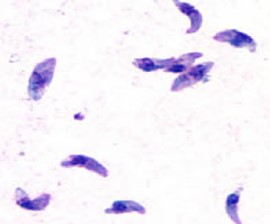

É uma zoonose de distribuição mundial, que acomete seres humanos e diversos animais, sendo o gato o hospedeiro definitivo do Toxoplasma gondii, o protozoário causador da doença.

Este parasita possui 3 formas principais: bradizoítos, taquizoítos e bradizoítos